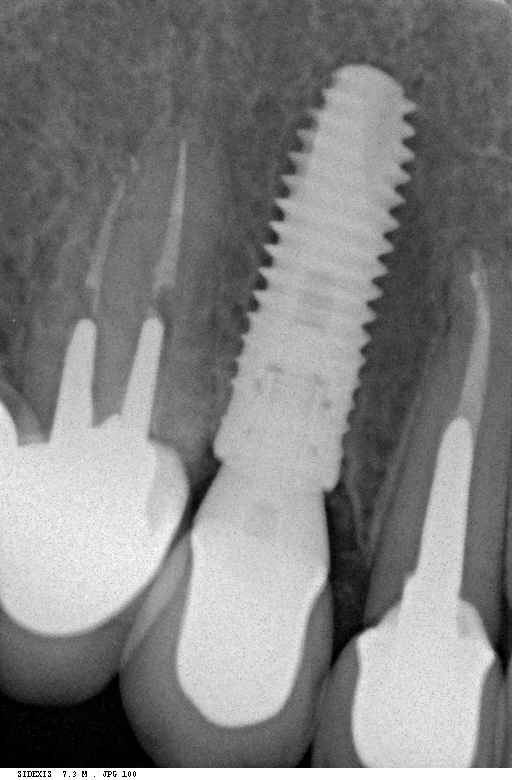

Рекомендации по установке имплантов. Для всех. Часть II.